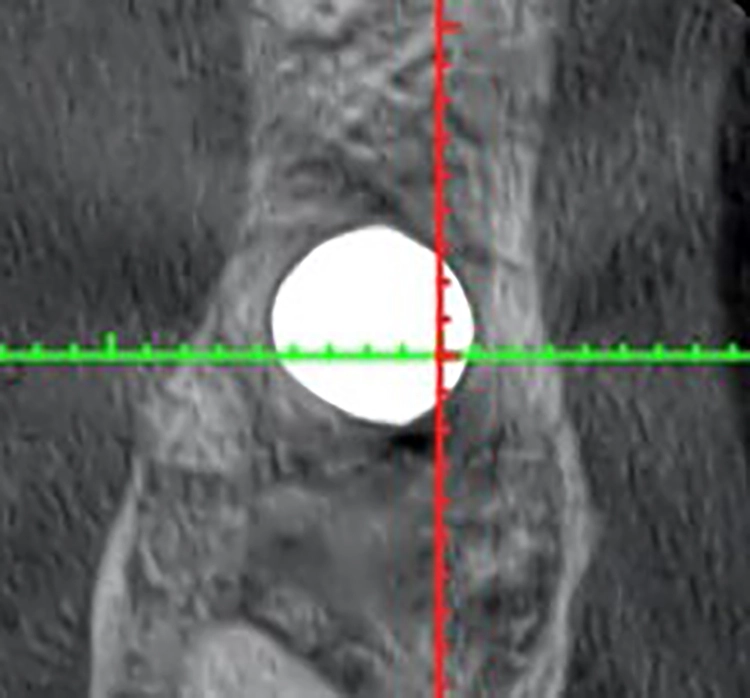

Mit dem primärstabilen WS-Condenser ø 4,3 mm wurde eine radiologische Messaufnahme durchgeführt. Dieser Fall wurde durch die neu geschaffene Kavität der IDS (interner, direkter Sinuslift) mit Smart Grinder-Material und dem im OP-Tray enthaltenen Ricci II-Instrument durchgeführt.

Gleich im Anschluss wurde ein CHAMPION (R)Evolution L 8 mm | ø 4,5 mm – ebenfalls im MIMI-Verfahren – mit einer Primärstabilität von 40 Ncm inseriert. Das DVT zeigt sehr deutlich die „weiße Wolke“ des Grinder-Materials, welches mehr Knochenwachstumsfaktoren enthält als Knochen selbst und durch die Schneider‘sche Membran optimal ernährt wird. Am gleichen Operationstag erfolgte die geschlossene Abformung samt Bissnahme (Abb. 20-23).